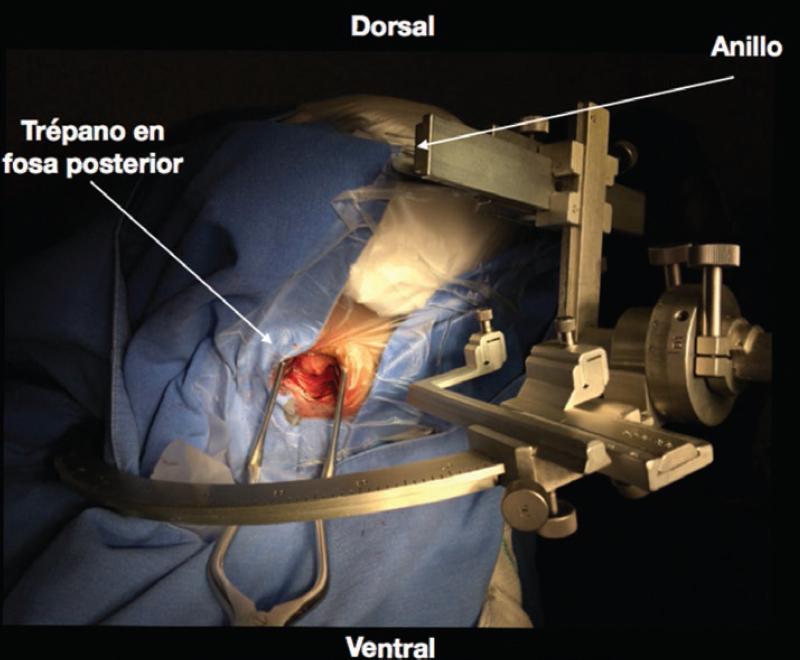

Para la técnica de estereotaxia con un equipo Zamorano-Dujovni, después de realizar antisepsia del área frontal y occipital con jabón quirúrgico, bajo anestesia local con xilocaína simple al 2% se realiza una infiltración en el sitio de los cuatro pinchos, dos frontales justo medial a la carilla lateral del frontal en cada lado, y dos occipitales, colocando el anillo estereotáctico invertido (postes dirigidos de arriba hacia abajo), con la marca de cero grados hacia delante y abajo, cuidando de dejar suficiente espacio para que cupieran las cuatro fiduciales sin quedar forzadas, especialmente la posterior y las dos laterales. Posteriormente se lleva al tomógrafo, se fija el anillo de estereotaxia a una base universal y se realiza la adquisición de una tomografía simple y contrastada de cráneo con cortes de no más de 1 mm. Se imprime la placa que corresponde a la localización exacta del sitio a biopsiar y se calculan manualmente las coordenadas lineales x (lateromedial), y (anteroposterior) y z (dorsoventral). En la mayoría de los casos se planeó solo el blanco y en algunos casos se planeó también el sitio de entrada, calculando las coordenadas angulares (ángulos alfa y beta) mediante cálculos de trigonometría (alfa = Tan−1 [dz/dy], beta = Tan−1 [dx/dM1M2]). Una vez en la sala de operaciones, con el paciente en decúbito supino, con la mesa quirúrgica en posición de Fowler y la cabeza del paciente flexionada, se realiza asepsia del área quirúrgica y colocamos los campos estériles. Bajo anestesia local, se infiltra con xilocaína al 2% con epinefrina, y se realiza incisión y disección por planos hasta llegar a la escama del occipital, donde se realiza un trépano. Se coloca el sistema de estereotaxia y se verifica en dos ocasiones la adecuada colocación de las coordenadas x, y y z. Se impregna la duramadre con xilocaína al 2% y se realiza coagulación e incisión (Fig. 1). Se introduce la cánula de biopsia previamente calibrada hasta llegar al blanco, en el cual se toman dos muestras de cada cuadrante, todo el tejido para estudio definitivo. Finalmente, se realiza el cierre de la manera habitual, sin dejar una burbuja de aire como marca, como en general se hace en las biopsias supratentoriales, por tratarse de la fosa posterior. Todo el tiempo se mantiene ocluida la endocánula o con solución, para evitar el neumoencéfalo, ya que la dirección de la cánula de biopsia en estos casos es de abajo arriba. El paciente se mantiene despierto o con sedación ligera durante todo el procedimiento.

Figura 1 Montaje del sistema estereotáctico Zamorano Dujovni, con el paciente en decúbito supino, en posición de Fowler, con la cabeza flexionada, el anillo dorsal y los postes y el sistema hacia abajo del paciente.